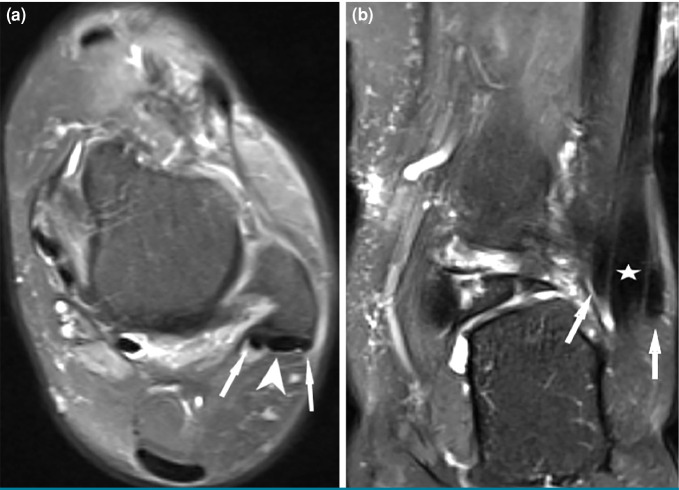

Patients and methods: Between January 2016 and December 2020, a total of 849 ankle MRIs (427 right foot, 422 left foot) in 738 patients (274 males, 464 females; mean age: 43.4±14.3 years; range, 15 to 70 years) were retrospectively analyzed. Among ankle pathologies, peroneal and flexor hallucis longus (FHL) tendinopathies were evaluated. Among the anatomical variations, retromalleolar fibular groove (RMFG) shape, os peroneum, os trigonum, peroneus quartus (PQ), flexor digitorum accessorius longus (FDAL), low-lying peroneus brevis (PB) and FHL muscles were examined. The distance of the PB and FHL musculotendinous junctions (MTJs) from designated reference points was measured. Cut-off values for PB and FHL musculotendinous junction distances were determined by receiver operating characteristic (ROC) analysis. For the reliability analysis of measurements performed by two researchers, intraclass correlation coefficient (ICC) values were calculated.

Results: Bilateral ankle MRIs of 111 patients were evaluated. The PB, PL, and FHL tenosynovitis were observed in 29.6%, 34.9%, and 38.8% of all ankles, respectively. The PB and PL tendon tears were found in 12.2% and 3.9%, respectively. A total of 47.1% of the RMFG shapes were concave, 36.7% were flat, 12.4% were convex, and 3.8% were irregular. The PQ, FDAL, os peroneum, and os trigonum were detected in 13.8%, 3.1%, 16.6%, and 20.5% of the ankles, respectively. The cut-off value of PB MTJ distance that would cause a PB tendon tear was 4.40 mm distal from reference point. The cut-off value of FHL MTJ distance that would cause FHL tendinopathy was 4.15 mm distal from reference point. The study had a statistically significantly high level of consistency between the experts (ICC=0.85).

Conclusion: The convex and irregular shapes of the RMFG, along with the anatomical variations of the os peroneum and low-lying PB muscle, constitute risk factors for peroneal tendon pathologies. The presence of the os trigonum and low-lying FHL muscle anatomical variations predispose individuals to FHL tendinopathies. The cut-off values that could lead to PB vertical tears and FHL tendinopathy were identified for the low-lying PB and FHL muscles, respectively.